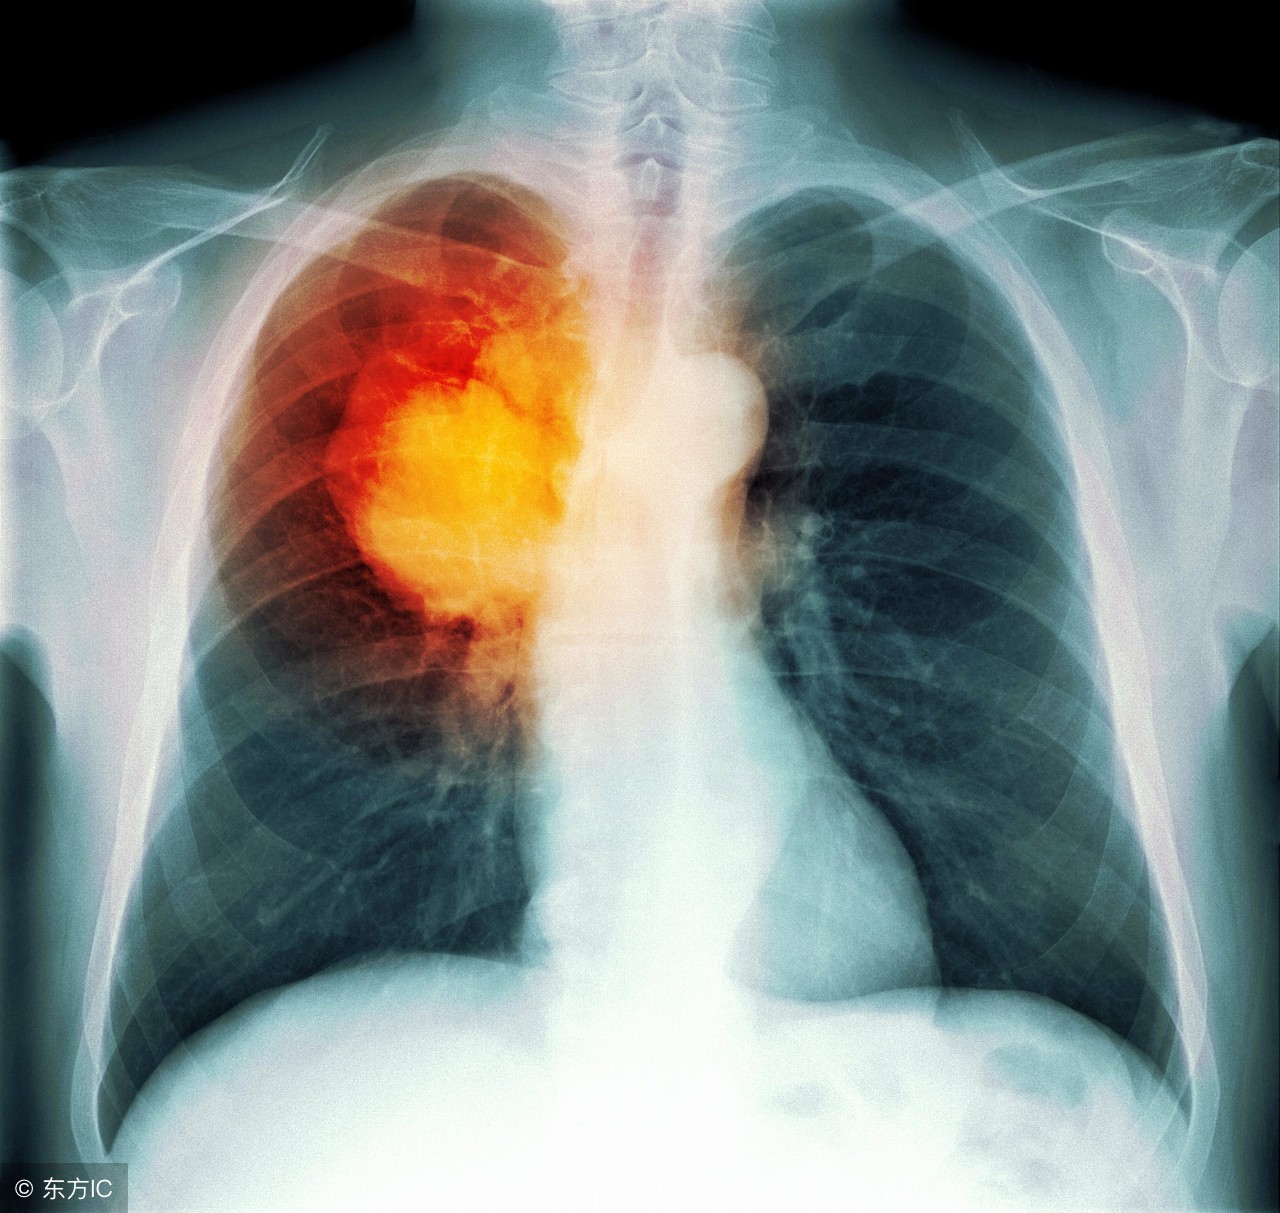

如今肺癌的诊断年龄正在越来越年轻。不想被肺癌缠上,你得尽早了解它。今天就来告诉你关于肺癌,肺结节的种种问题。

2、哪种类型的肺结节可能导致癌症?

基本上任何类型都可能导致肺癌,较大的结节患肺癌几率更大,结节越大,患肺癌的可能性就越大。结节越大,死于肺癌的几率就越大。

早期筛查非常重要,当结节还小的时候尽早发现它手术也会小很多。做手术时打几个小洞,切除一点肺。结节变大,手术也变大,需要开胸然后取出更多的肺。